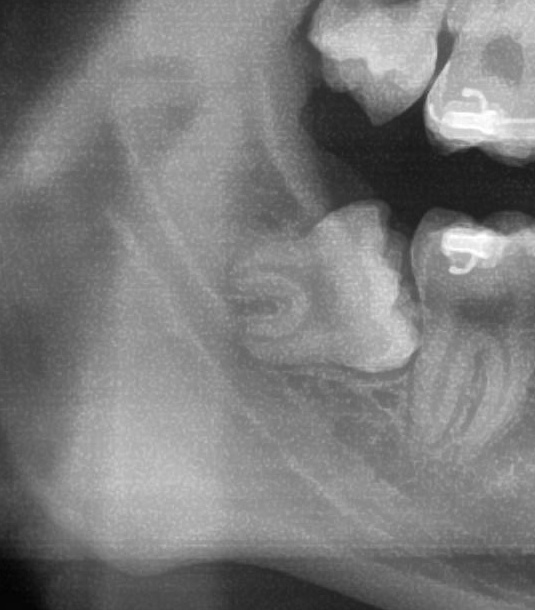

次にパノラマ写真を撮影してみると、右下の親知らずは手前の歯を押すように斜めに生えているのが確認できました。